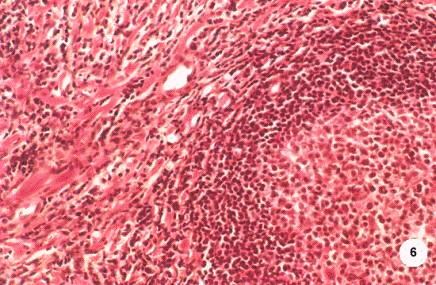

Рис. 6

Хроническое воспаление стромы предстательной железы тяжелой степени. Сливающиеся зоны лимфоцитарной инфильтрации с формированием фолликулов и отеком.